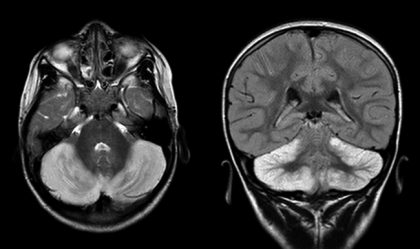

Cerebelitis aguda

En cuanto a la cerebelitis aguda, explicó que es la inflamación del cerebelo, órgano encargado de la coordinación del movimiento de cuerpo. “Esto ocasiona que el paciente no tenga una posición estable, que camine como borrachito. Aunque este mal se autolimita y suele tener buena evolución sin secuela en la mayoría, es importante acudir al médico para evitar problemas posteriores sobre todo en los niños”, detalló el médico.